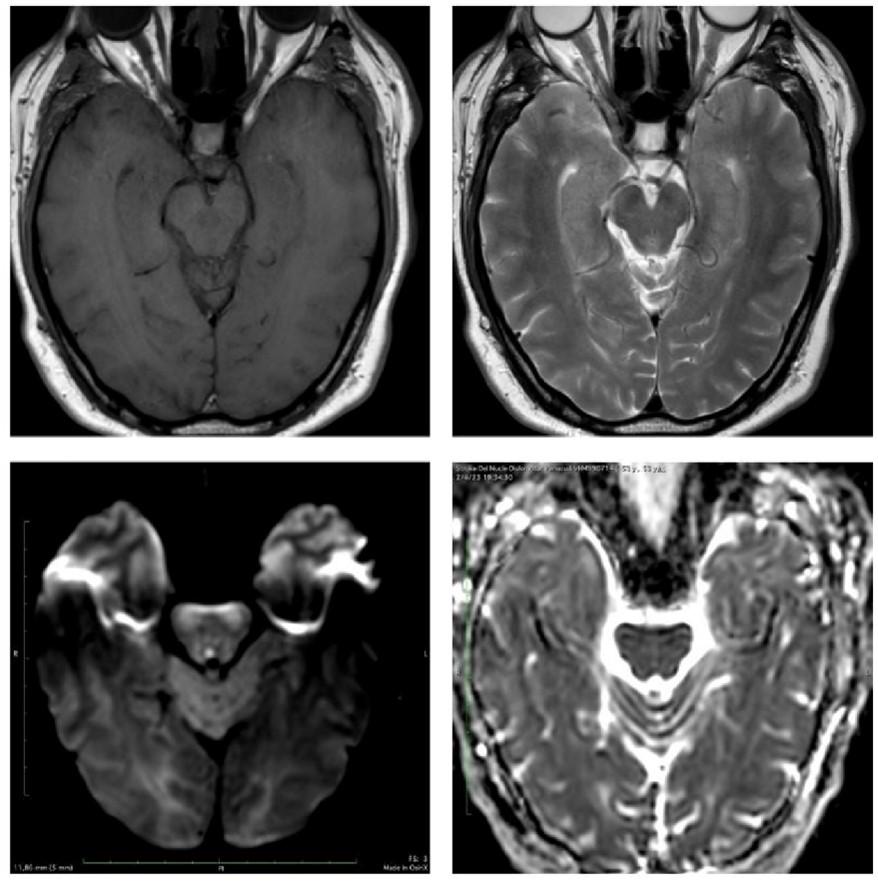

La lesión se localiza en el puente dorsomedial, en una topografía correspondiente al colículo facial, región formada por el núcleo del nervio abducens y las fibras intrapontinas del nervio facial que lo rodean. Este territorio se asocia clásicamente con el síndrome del colículo facial, caracterizado por la afectación de los circuitos oculomotores horizontales y del nervio facial.(5, 11, 12)

Desde el punto de vista anatómico, el compromiso del núcleo del VI par y de la formación reticular paramediana puede explicar la alteración de la mirada horizontal ipsilateral, mientras que la afectación de las fibras del nervio facial justifica la parálisis facial periférica ipsilateral. La ausencia de una extensión ventral significativa hacia la base del puente favorece este diagnóstico frente a otros síndromes pontinos mediales, como el síndrome de Foville, que típicamente asocia compromiso del tracto corticoespinal.(11, 12)

Caso 5

El compromiso de la porción basal del puente implica estructuras críticas, como los núcleos o fascículos de los nervios craneales VI y VII y la vía corticoespinal, configuración anatómica característica del síndrome de Millard-Gubler, un síndrome pontino ventromedial perteneciente al grupo de los síndromes alternos del tronco encefálico, descrito en asociación con múltiples etiologías y presente en todos los grupos etarios. En población joven predominan las lesiones tumorales e infecciosas, mientras que las causas vasculares, tanto isquémicas como hemorrágicas, son menos frecuentes.(13)

A diferencia de los infartos pontinos dorsales, en los que predomina el compromiso de estructuras oculomotoras y del tegmento pontino, la localización ventral observada en este caso explica la asociación de déficit motor contralateral con signos de afectación de los pares craneales ipsilaterales, patrón sindrómico clásico descrito para el síndrome de Millard-Gubler. La extensión de la lesión hacia la base del puente, sin compromiso dorsal significativo, permite diferenciar este síndrome de otras entidades pontinas mediales, como el síndrome del colículo facial o el síndrome de Foville, en los que el tegmento dorsal se encuentra involucrado.(15)